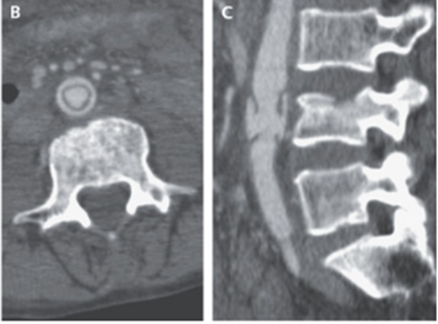

造影CT検査では、L4前方の腹部大動脈の全周性内膜破壊を認めたこと(B)とL4椎骨骨折(C)があきらかになった。造影剤の大動脈血管外漏出や大動脈解離、血栓症は認めなかった。